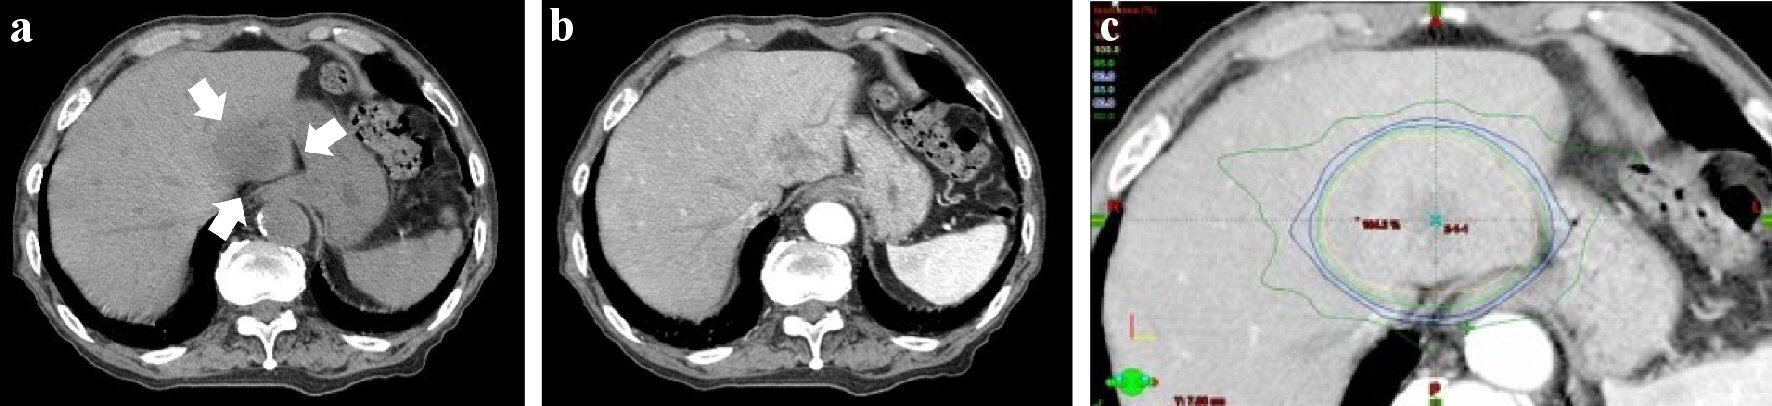

The size of HCC in hepatic segment 2 reduced after TACE. However, it recurred and grew up to 4 cm in size afterwards (Fig. 2a, b). His Eastern Cooperative Oncology Group (ECOG) performance status was grade 0, Child-Pugh score was class A. He was tried TACE for HCC once again, but it failed because the access to responsible vessel was difficult. He received radiotherapy for HCC (SBRT, radiation on alternate days, the total dose: 49.0 Gy in seven fractions (48.4 Gy to the lower esophagus)) in the S2 segment from the beginning to the middle of December, 2017 (Fig. 2c). He did not have the symptom at the end of the radiotherapy. He did not visit our hospital for follow-up due to his self-judgment afterwards.

![]() Click for large image | Figure 2. Abdominal computed tomography (CT) of December 2017, before radiotherapy. (a) Abdominal CT (plain). (b) Abdominal CT (contrast-enhanced; arterial phase). (c) Dose distribution (isodose distributions: yellow line 100%; inside/green line 95%; blue line 90%). There was a low density area (about 4 cm in size; white arrow) in hepatic segment 2 for abdominal plain CT. It was well-enhanced in the arterial phase for contrast-enhanced CT. The lesion was close to the gastroesophageal junction. The lower esophagus and the cardia of the stomach were included in the range of the radiation (yellow arrow head). The total dose to HCC was D0.5 cm3 = 49.0 Gy, the lower esophagus: D0.5cm3 = 48.4 Gy. |